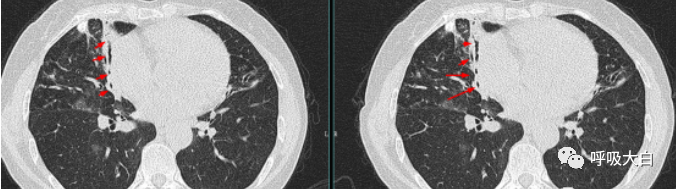

支气管形成的“轨道征”是由于支气管管壁和支气管周围纤维化,使支气管管壁增厚,当X线平面与相应支气管长轴平行时,由于增厚支气管壁之间的管腔内有气体衬托,影像上形成两条平行线状密度增高影,表现为轨道样阴影或呈管状阴影,称轨道征或管状阴影。

支气管形成的“轨道征”病理机制主要为支气管管壁和支气管周围反复炎症使支气管管壁纤维化、增厚阻塞,管壁结构(平滑肌、弹力纤维甚至软骨等)破坏,同时管内压增加或邻近肺内纤维化等外力的牵拉,使相应支气管柱状扩张。少数病例与先天遗传因素有关。